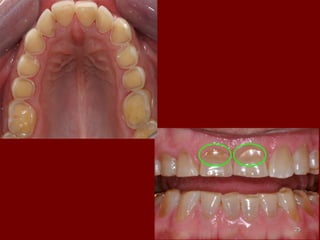

ATTRITION DUE TO BRUXISM.ATTRITION DUE TO BRUXISM.

ATTRITION DUE TOBRUXISM.ATTRITION DUE TO BRUXISM. 99